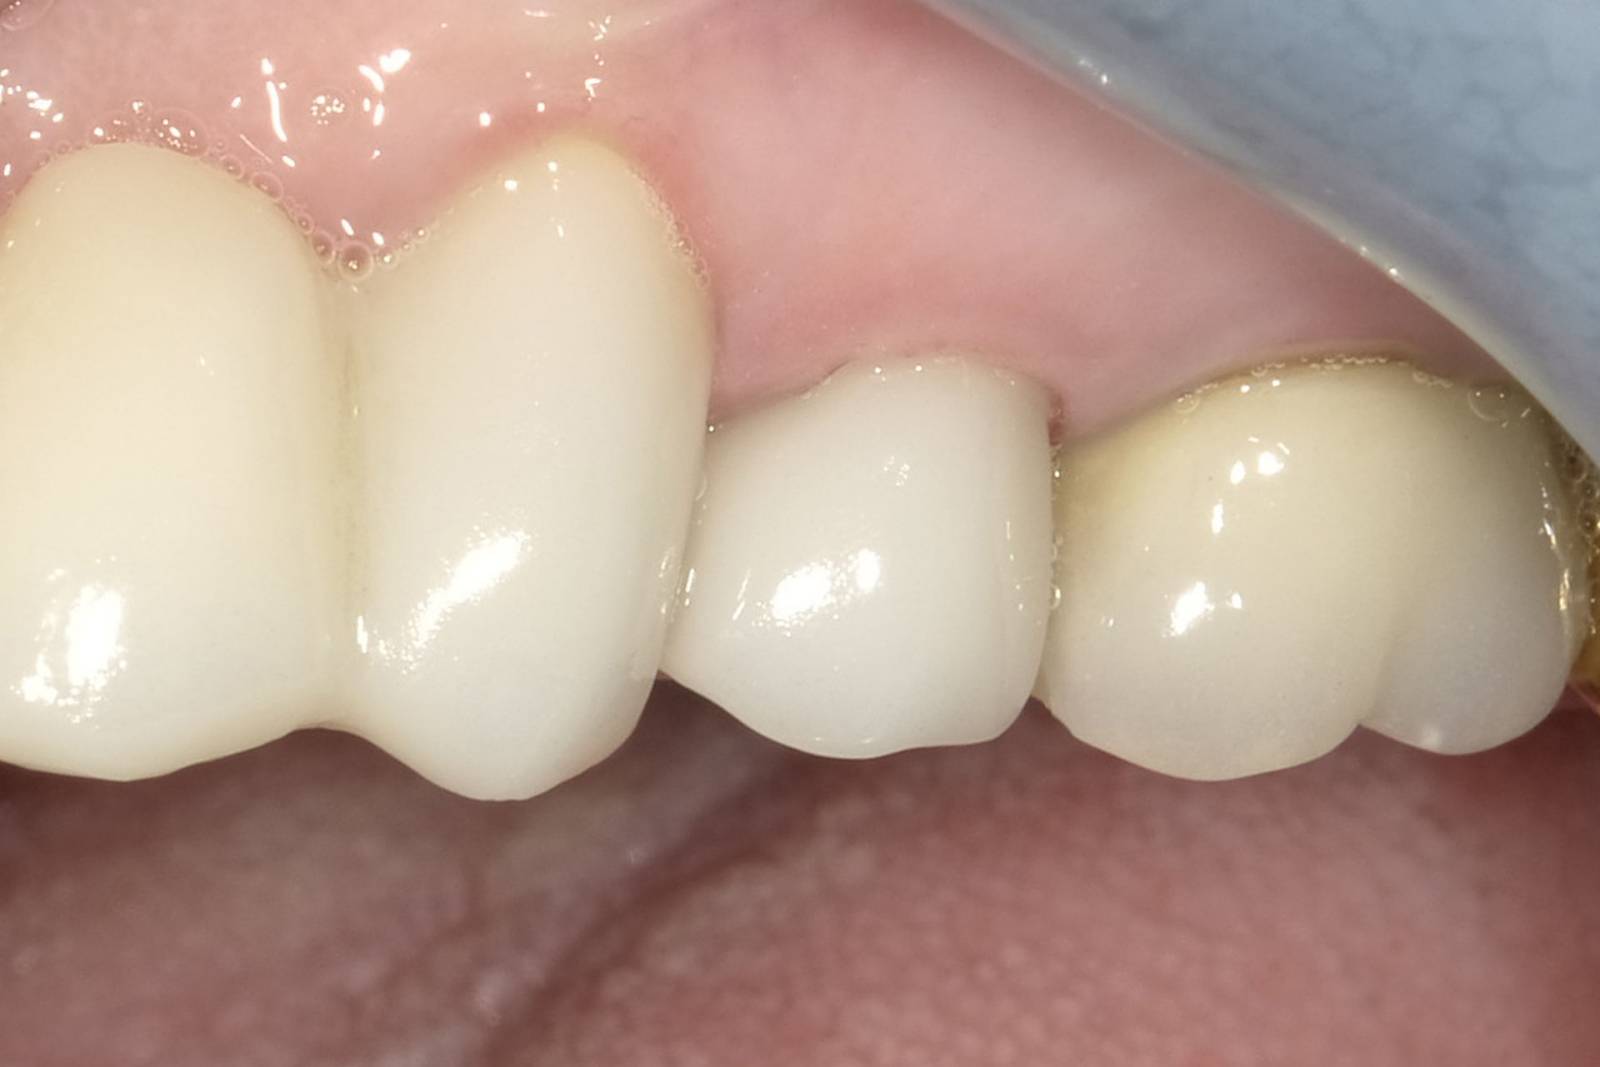

After

Chairside-fabricated restoration made from an advanced lithium disilicate ceramic, CEREC Tessera.